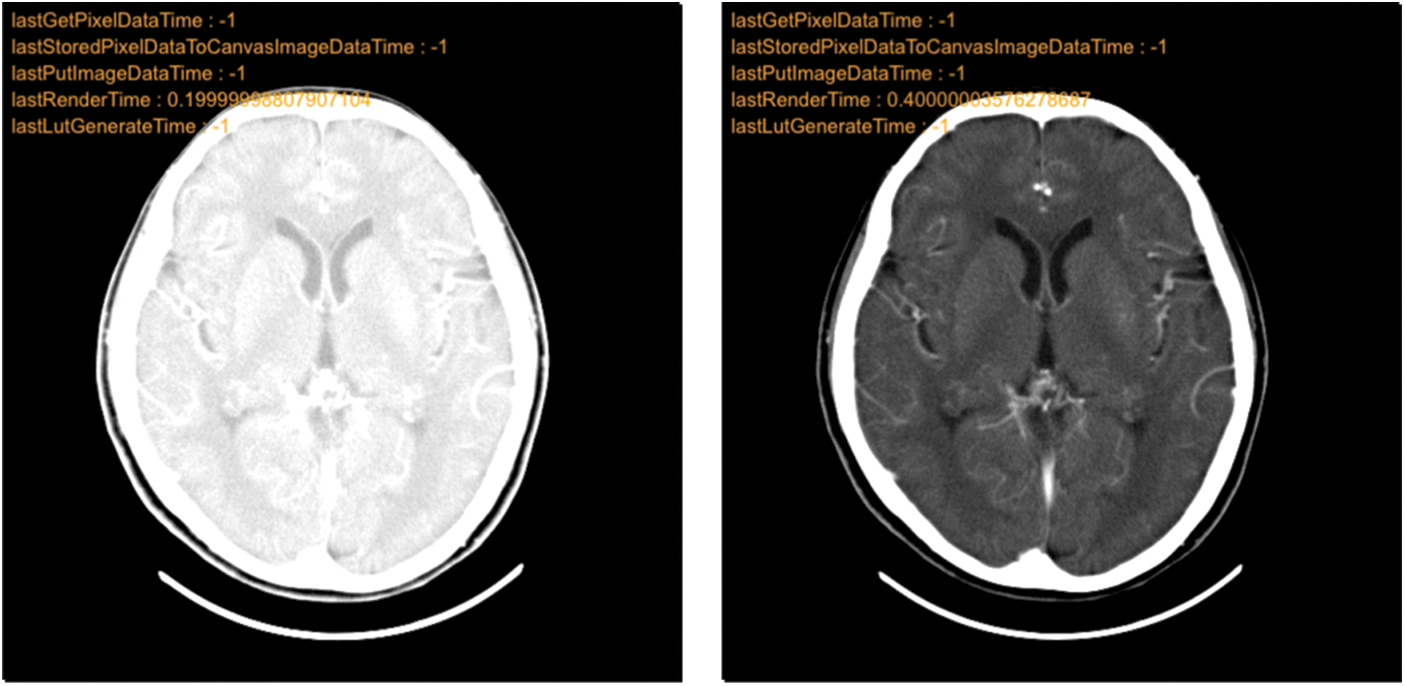

Additionally, Cornerstone’s integration facilitates grayscale value [44] adjustments, aiding doctors in making more informed decisions. An example of grayscale adjustment is presented in Fig. 12.

Figure 12: Grayscale adjustment comparison chart